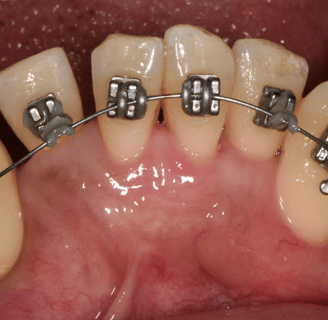

Orthodontiste

Orthodontie